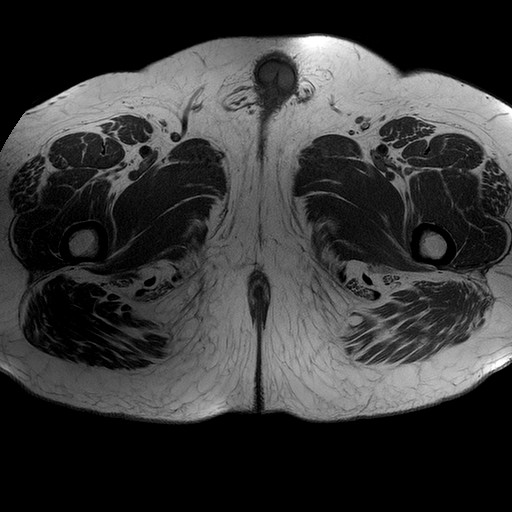

Esami: RMN BACINO

T1W_TSE

Evidenti e simmetriche alterazioni osteofitosiche in regione coxo femorale con riduzione delle rime articolari. Degenerazione completa del cercine glenoideo. Non attuali segni di versamento articolare. Non segni di edema osseo che escludono attuale algodistrofia od osteonecrosi. Lieve e simmetrica riduzione del trofismo della muscolatura glutea.